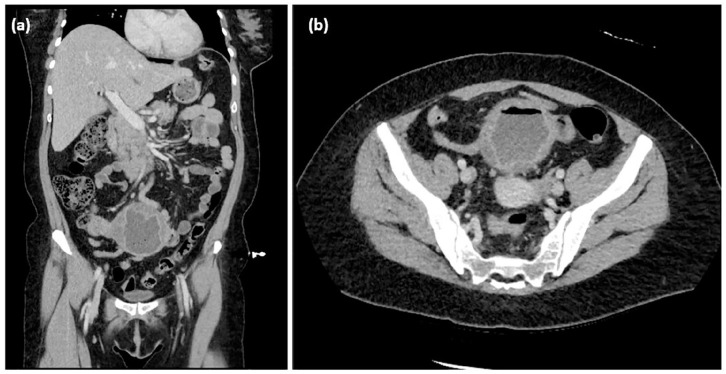

子宫内膜异位症是一种妇科疾病,可出现在盆腔和盆腔外部位,包括胃肠道。盲肠和阑尾受累是罕见的,可以表现为贫血,模仿恶性肿瘤。本病例为一50岁女性,表现为症状性贫血。影像显示盲肠及阑尾肿块伴淋巴结病变,可能为恶性肿瘤。结肠镜检查显示可疑肿瘤,但活检结果不确定。手术切除发现广泛的子宫内膜异位症累及盲肠和阑尾。病理证实酷似子宫内膜异位症。术后,患者的贫血得到改善。本病例强调胃肠道子宫内膜异位症通常无症状且难以诊断。其结肠肿块的表现强调了广泛区分的必要性。当怀疑有恶性肿瘤时,手术干预至关重要。

Endometriosis is a gynecological condition that can manifest in pelvic and extra-pelvic sites, including the gastrointestinal tract. Cecal and appendiceal involvement is rare and can present as anemia, mimicking malignancy. The discussed case is of a 50-year-old female who presented with symptomatic anemia. Imaging revealed a cecal and appendiceal mass with lymphadenopathy, raising concern for malignancy. Colonoscopy showed a suspicious tumor, but biopsy was inconclusive. Surgical resection revealed extensive endometriosis involving the cecum and appendix. Pathology confirmed endometriosis mimicking neoplasia. Postoperatively, the patient's anemia improved. This case highlights that gastrointestinal endometriosis is often asymptomatic and difficult to diagnose. Its presentation as a colonic mass underscores the need for broad differentials. Surgical intervention is crucial when malignancy is suspected.